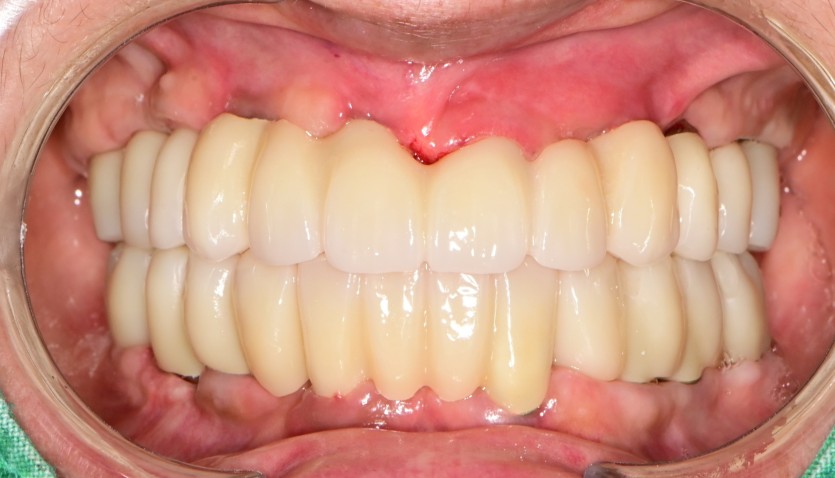

만 58세 전체 임플란트 증례입니다.

18개의 임플란트로 완성하였습니다.